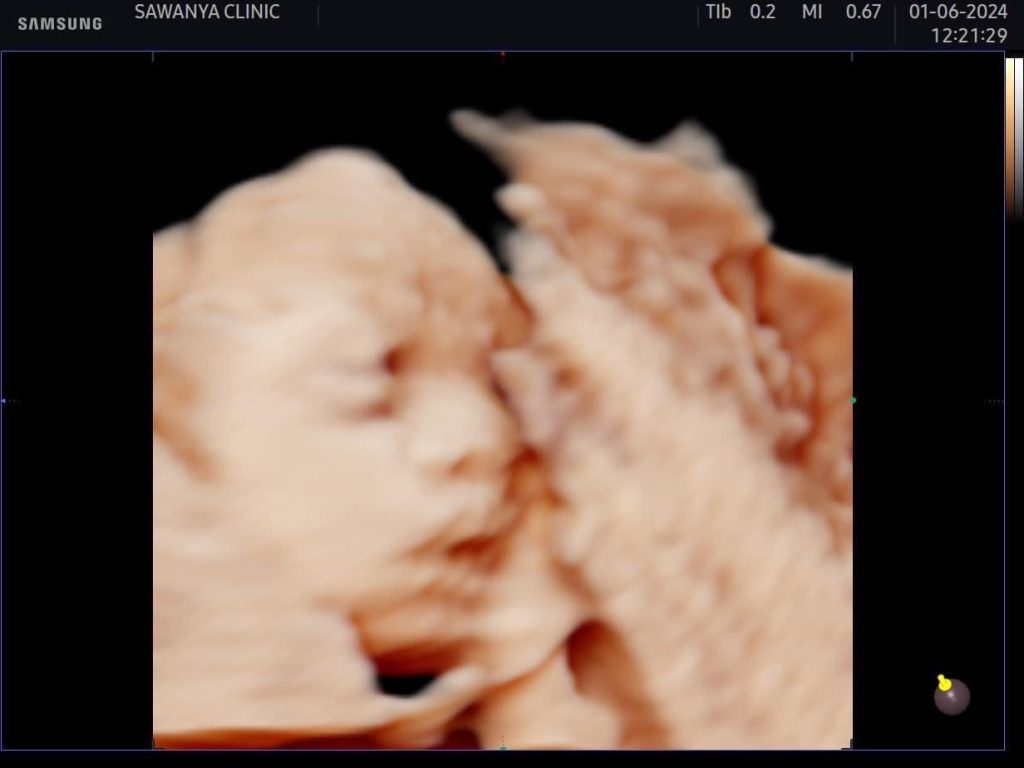

ทำเอาคุณแม่มือใหม่อย่าง ธัญญ่าอาร์สยาม ใจฟู ได้เห็นวิวัฒนาการของลูกใน 27 สัปดาห์

บอกเลยอะค่ะเตรียมตัวรับมือการเป็นคุณแม่ป้ายแดงที่จะได้เจอหน้าลูกในเร็ววันนี้ด้านธัญญ่าตื่นเต้นเตรียมของต้อนรับสมาชิกใหม่ไวให้ลูกเต็มบ้าน และ คอยอัพเดทผ่านโซเชียลให้กับบรรดาเอฟซีแฟนคลับได้ลุ้นรอเชียร์กันไปตามตามกันแล้วค่ะ